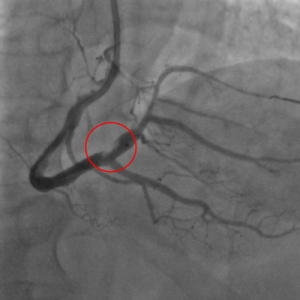

機械式血栓抽吸裝置清除血栓 花蓮慈院團隊救回急性心肌梗塞患者

花蓮慈濟醫院心臟科團隊日前在心導管室成功將一名出現大範圍血栓的急性下壁心肌梗塞患者,從鬼門關搶救回來。心臟內科心功能檢查室主任劉維新指出,患者一度出現心因性休克,急救後仍心跳不穩,不僅裝置葉克膜,最後因使用「機械式血栓抽吸裝置」協助抽出血栓,才成功置放支架;患者目前恢復良好,已順利出院。